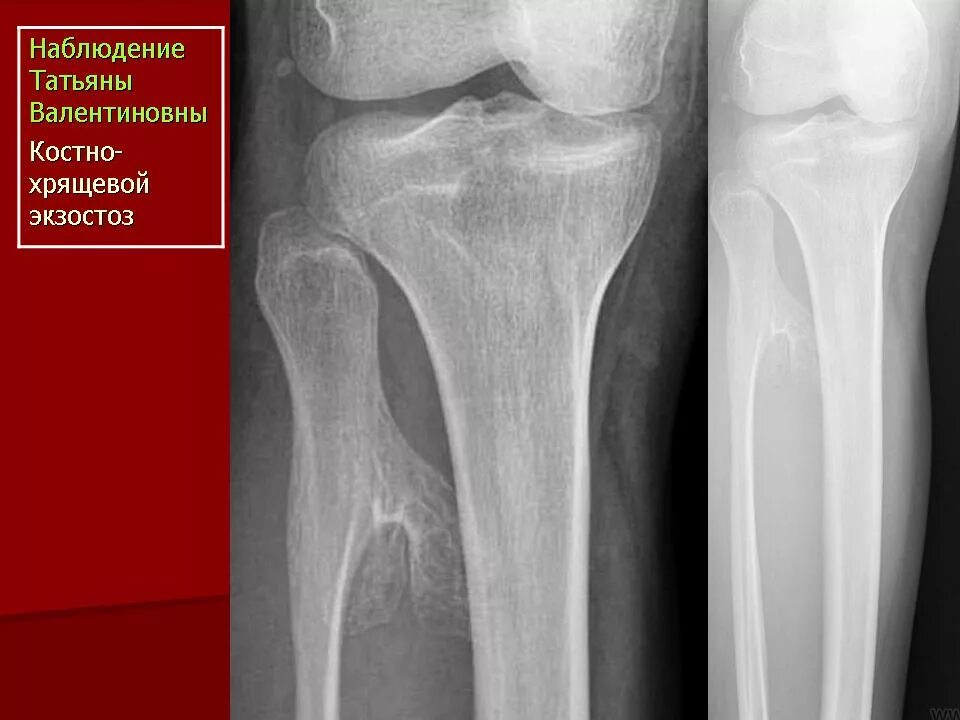

Экзостоз мкб 10